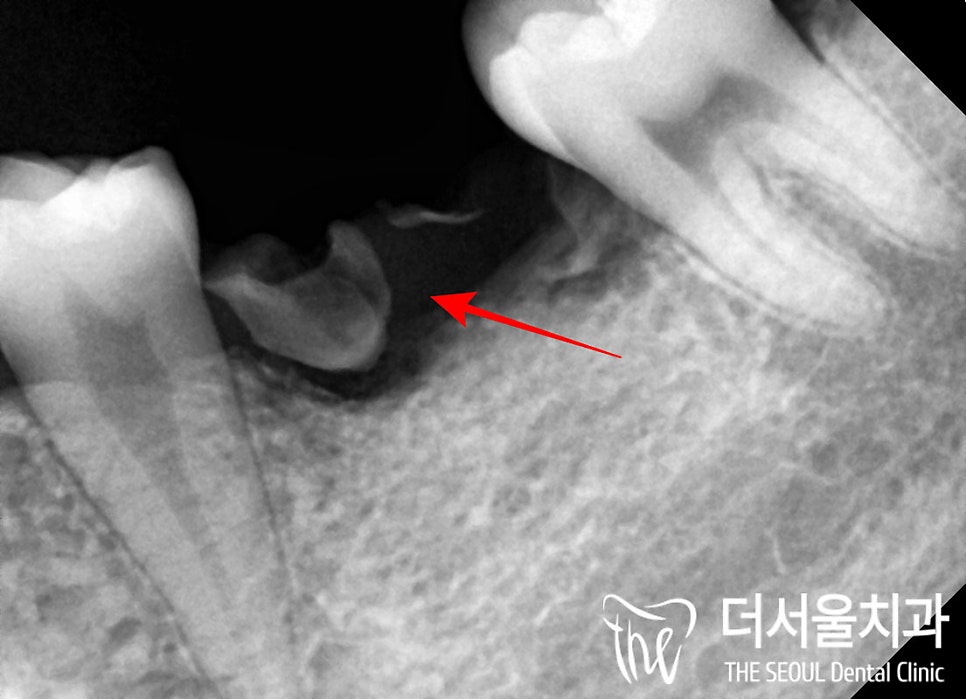

2. 정밀 진단

성남 치과 에서는

육안으로 1차 검사를 한 뒤,

엑스레이를 찍어

정확한 상태를 한 번 더 파악하는데요,

파노라마를 보면

예측했던 대로

심한 우식으로 인하여

주된 저작기능을 해야 되는

어금니들이 부러지고

깨져있습니다.

혹시 살릴 수 없을까

치근단 사진을 찍어보았으나

이미 치근분지부까지

우식 범위가 넓게 퍼져있었으며

부러진 이들은

치조골 내에서

염증을 일으키며

뼈를 녹이고 있었습니다.